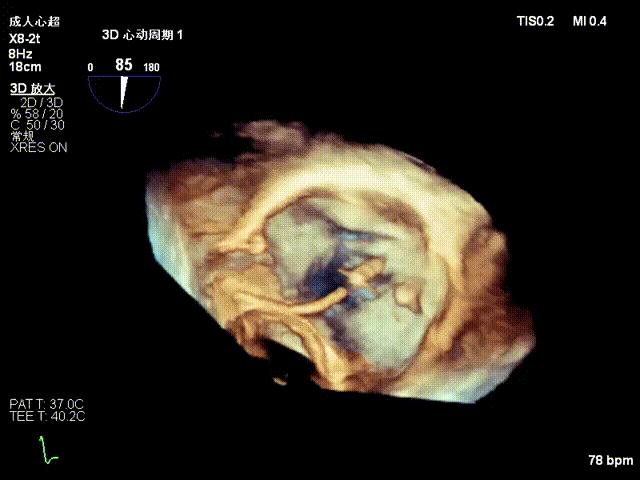

2.Annuloplasty Effect: Annular morphology remodeled, central gap significantly reduced.

Preoperative 3D

Postoperative 3D